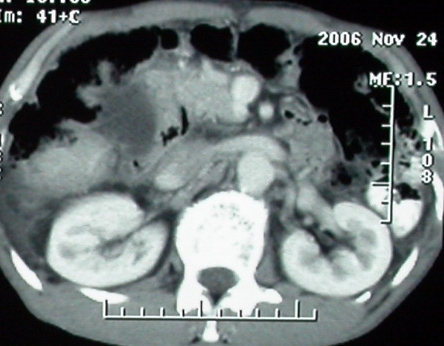

ct表现:1,胰腺钩突后方肿块,不均强化,中心密度低,钩突及门静脉前移。2:肝右后叶不均强化灶,突出肝表面,3:胆囊明显增大,肝内胆管及肝总管内积气。4:腹腔内少量积液。

胰头后方肿块,周边强化,胰头受压推移,肝脏右后叶异常强化灶,首先考虑肝癌后腹膜淋巴结转移;2、肝内胆管积气。

手术结果:

肝脏尾状叶肝癌(沿肝十二指肠韧带向下韧带内生长,门腔间隙外压增大),大结节性肝硬化,胆囊积脓,胆道感染。术中见肝外胆道2cm直径,肿瘤向前压迫胆管至扁平状态。